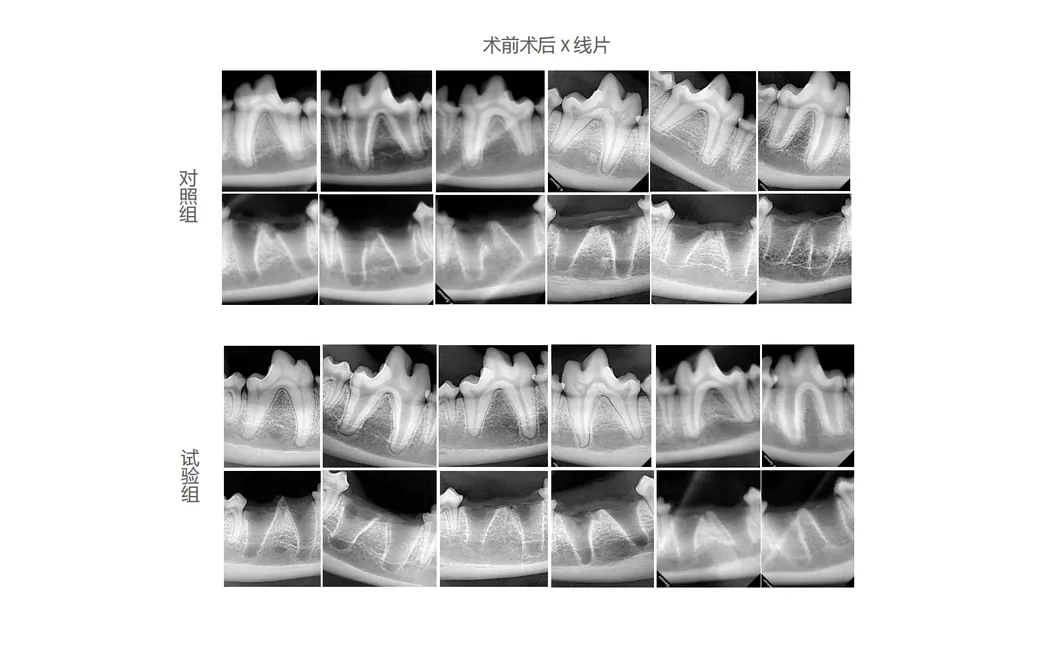

In this study, the efficacy of state-of-the-art dental instruments was evaluated. The experimental group used the Golden Cudgel-Pneumatic Dental Elevator Kit. Researchers analyzed physiological parameters, frequency of complications, duration of extraction, and trauma levels. The data scrutiny provides insights into the enhanced efficiency and superior performance of these advanced dental tools.